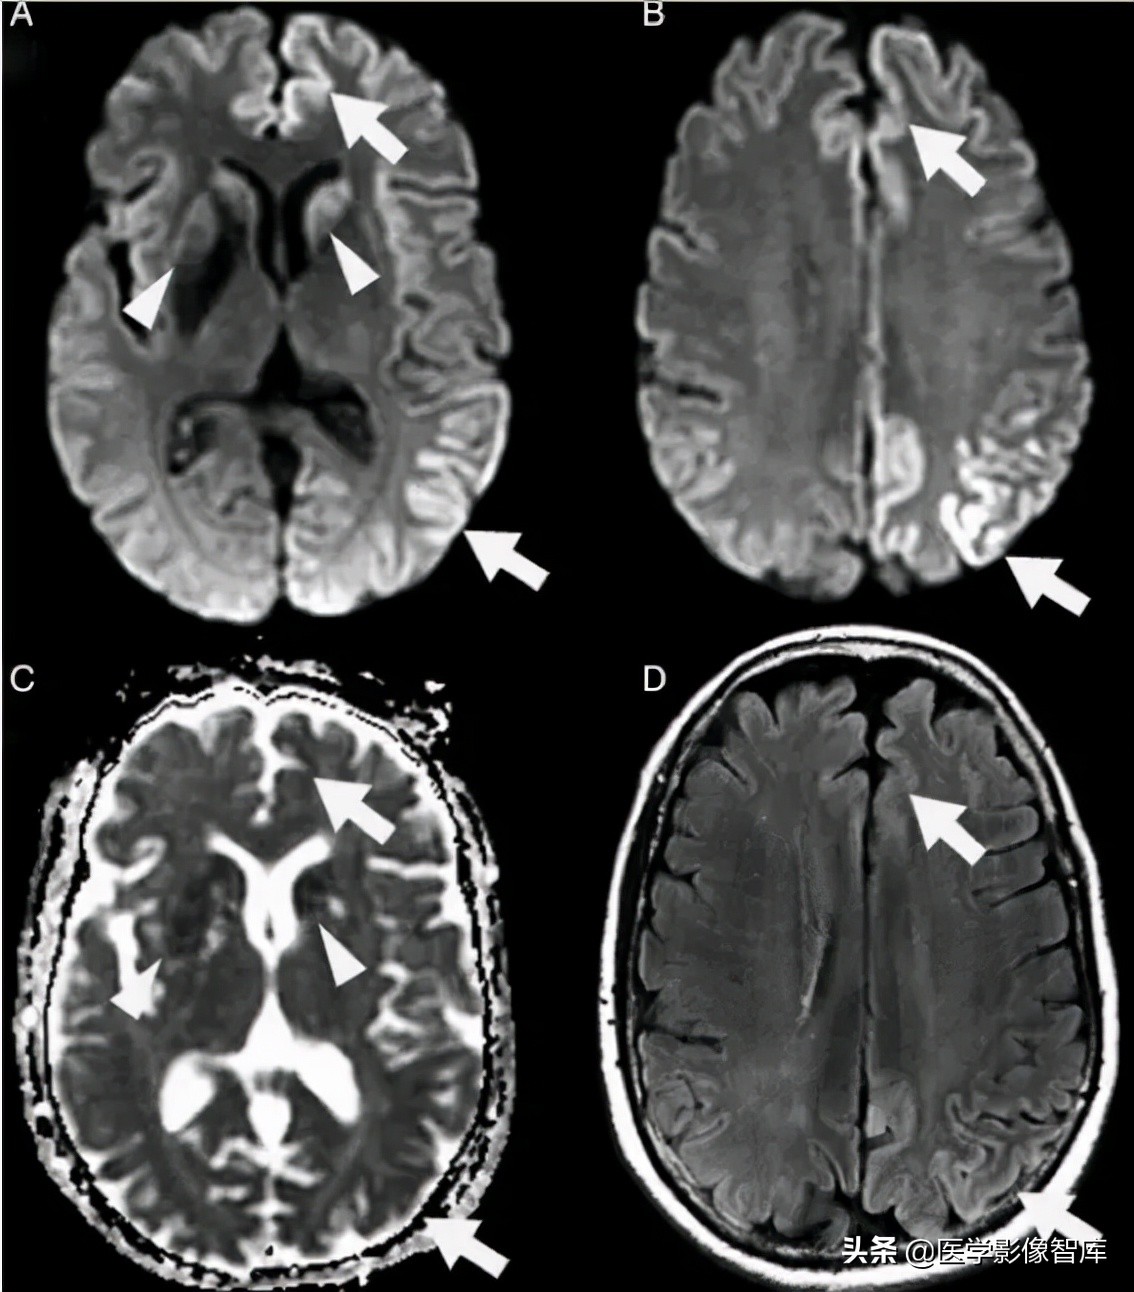

克雅病(CJD,Creutzfeldt–Jakob disease)是由朊蛋白病毒所致的一类具有传染性、进行性恶化的神经系统变性疾病,主要表现为进行性痴呆、精神障碍、肌阵挛等。病程后期脑电图可见特异性的三相波,部分患者脑脊液 14-3-3 蛋白阳性。此种病目前为止没有任何有效的治疗方式,患者在出现临床症状后一般在半年至两年内死亡。CJD 早期无影像异常,中晚期常出现一些影像异常,比较典型的有花边征(cortical ribbon,又叫飘带征,特点即为皮质 DWI 高信号,常见于散发型 CJD),曲棍球征(hockey-stick sign,指双侧丘脑枕和背内侧丘脑同时对称性受累的 T2、DWI 高信号病变,常见于变异性 CJD)。临床上,进行性痴呆、椎体 / 椎体外系症状、脑电图异常(三相波)患者若出现花边征,常常指向 CJD。图 3 显示一个散发型 CJD 患者磁共振检查结果。

图 3 花边征(飘带征),散发型 CJD 患者,A、B 为 DWI,C 为 ADC 图,D 为 FLAIR。可见患者双侧皮层不对称的 DWI 高信号(箭头),基底节区 DWI 高信号(三角箭头),病灶 ADC 图上为低信号,FLAIR 上高信号